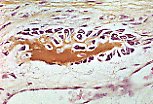

Ce prélèvement a

été réalisé dans la voûte crânienne, au niveau de de l'ébauche d'un os pariétal

chez un embryon âgé de trois mois.

Sous le cuir chevelu, reconnaissable à son épiderme et ses ébauches de follicules pileux , se remarquent quelques travées osseuses disposées sur deux étages. Elles sont constituées de tissu osseux non lamellaire . Chacune de ces petites travées est un centre d'ossification membraneuse résultant d'une métaplasie directe du tissu mésenchymateux en tissu osseux. Elles se rejoindront ultérieurement pour former un véritable réseau. |

Cette coloration de Von Kossa permet de souligner la partie minéralisée des travées osseuses en brun tandis que la dernière couche déposée par les ostéoblastes (liseré pré-osseux ou zone ostéoïde) est colorée en jaune. |